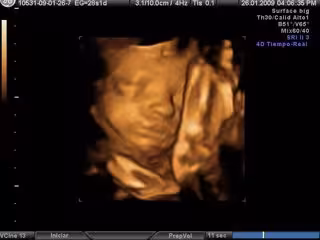

Ecografía en 3D- embarazo

Los fetos de más de 16 semanas y que miden al menos 11 centímetros mueven la boca de forma exagerada cuando escuchan la voz materna o una voz humana, llegada a través de un dispositivo intravaginal desarrollado con este objetivo, ha informado el Institut Marquès de Barcelona este miércoles.

Además, el nuevo reproductor de sonido también permite descartar la sordera fetal y facilita hacer las ecografías al provocar una respuesta en el bebé y así mejorar la visión de las estructuras fetales.